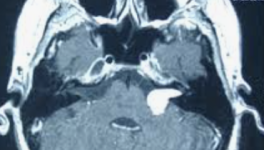

C’est la combustion des feuilles (ici de tabac) qui relâche les substances cancérigènes.

Lors de l’aspiration, une bouffée de cigarette libère une phase particulaire (ou condensat) faite de goudrons (avec plus de 4000 substances cancérigènes), d’eau et de nicotine et une phase gazeuse avec en particulier du monoxyde de carbone (CO) qui bouche les artères beaucoup plus sûrement et efficacement que n’importe quelle autre pathologie (diabète/hypercholestérolémie…).